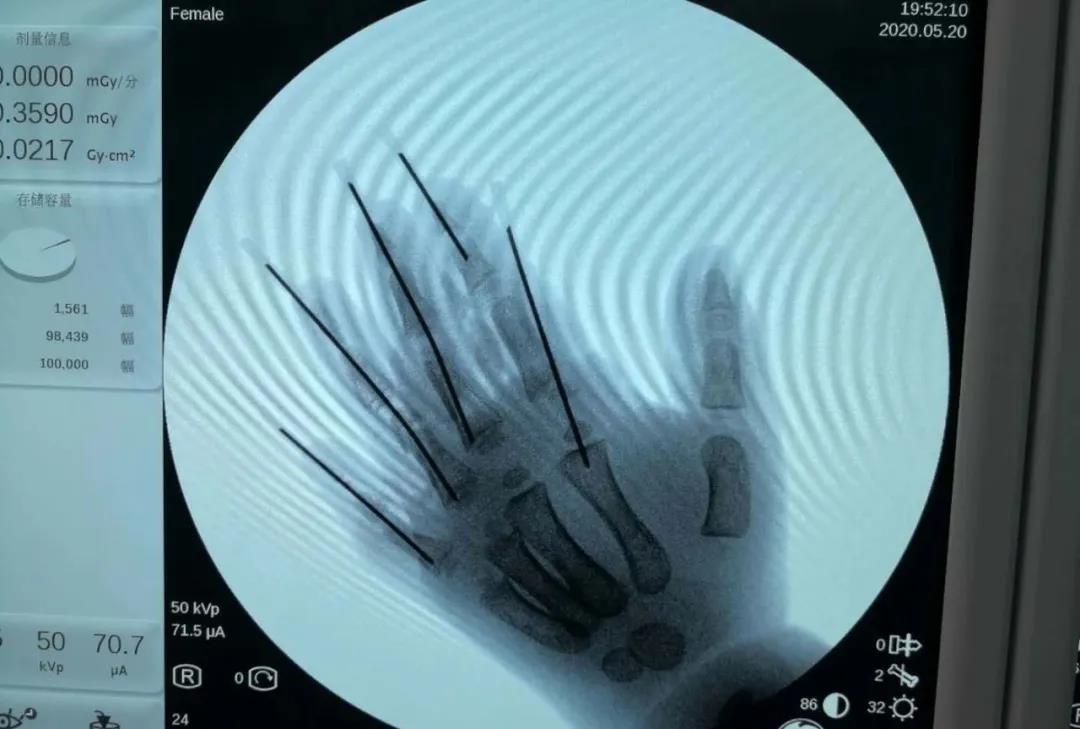

一切準(zhǔn)備就緒,下午3點(diǎn)多,手術(shù)開始。首先,何旭主任對(duì)兮兮的左手手指?jìng)谶M(jìn)行清創(chuàng),將油污和壞死組織清理干凈。緊接著,何旭主任在透視機(jī)下仔細(xì)觀察斷裂的骨頭、關(guān)節(jié),用克氏針將斷裂的指骨關(guān)節(jié)接好,將骨頭復(fù)位固定。然后,何旭主任小心翼翼地將肌腱、神經(jīng)、血管一一接好,經(jīng)過5個(gè)小時(shí)的努力,手術(shù)順利完成。

圖源:青島市中心醫(yī)院

術(shù)后,兮兮左手3-5指血運(yùn)良好,顏色紅潤(rùn),但食指指尖因挫傷太重,壞死了。5月31日,何主任為兮兮進(jìn)行二次手術(shù),術(shù)中去掉了食指壞死的指尖。經(jīng)過治療,兮兮的左手傷口已經(jīng)愈合,于6月9日出院了。